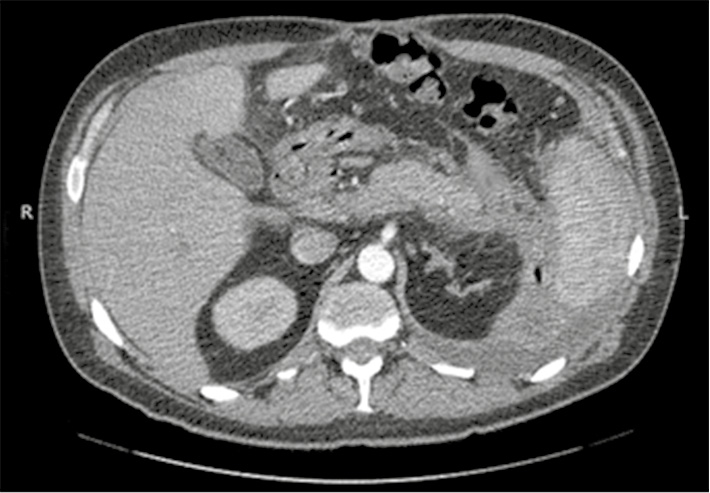

On days 2-3, there was an intake of stagnant gastric contents via a nasogastric tube , bloating, gas retention, a gradual increase in leukocytosis up to 1 4 , 5 * 10 * 9 / l with a stab shift to the left up to 18% , amylase up to 36 mg / s * l ... On the 3rd day, according to the drainage from the omental bursa, the intake of serous-hemorrhagic discharge up to 300 ml was noted. A biochemical study of the discharge obtained amylase up to 9 4 mg / s * l. Ultrasound of the abdomen showed a diffuse enlargement of the pancreas, the presence of fluid accumulation in the parapancreatic tissue . Computed tomography of the abdominal cavity revealed pancreatic edema , infiltration of parapancreatic tissue, accumulation of fluid in the cavity of the omental bursa (Fig. 1) . Specify an diagnosis: traumatic punk p e Amum, a moderate course. Assigned to The appropriate medical therapy . By the end of 5 days after the operation on the background of the therapy laboratory values were normalized (amylase Blood 12 , 0 mg / s * l, leucocytes 10.2 * 10 * 9 / L ) . On the 8th day, the probe was removed and the patient was transferred to the general department. On the 21st day, the patient is presented at the IHC . Final diagnosis: Gunshot bullet blind penetrating blind wound of the abdomen with a penetrating wound of the anterior wall of the lower third of the stomach. Traumatic shock of the 1st degree. Acute rheumatic pancreatitis , mild course.

Figure: 1. Computed tomography of the abdomen with bolus contrast . Nonspecific CT scans of traumatic pancreatitis: edema of the pancreatic parenchyma, infiltration of parapancreatic tissue, accumulation of fluid in the cavity of the omental bursa